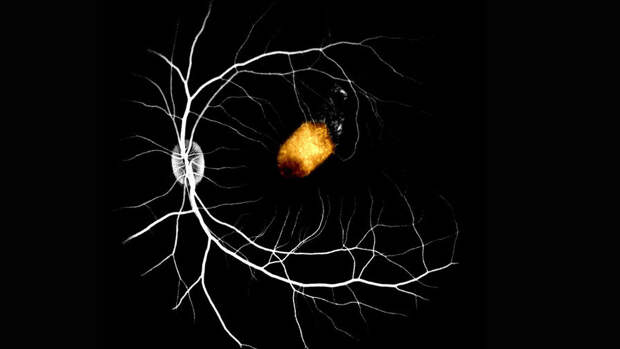

Исследователи использовали стволовые клетки сетчатки, полученные от двух умерших пожилых людей. Они пересадили их на желтое пятно - место наибольшей остроты зрения в сетчатке - девяти макак. Эксперимент проводился пока что на здоровых животных, чтобы понять, возможна ли вообще подобная пересадка.

Клетки успешно прижились, на протяжении трех месяцев не наблюдалось никаких серьезных побочных эффектов.Более того, пересаженные клетки оказались способны взять на себя функции пигментного эпителия сетчатки обезьян, что дает потенциальную возможность в будущем использовать такой метод для борьбы со слепотой.